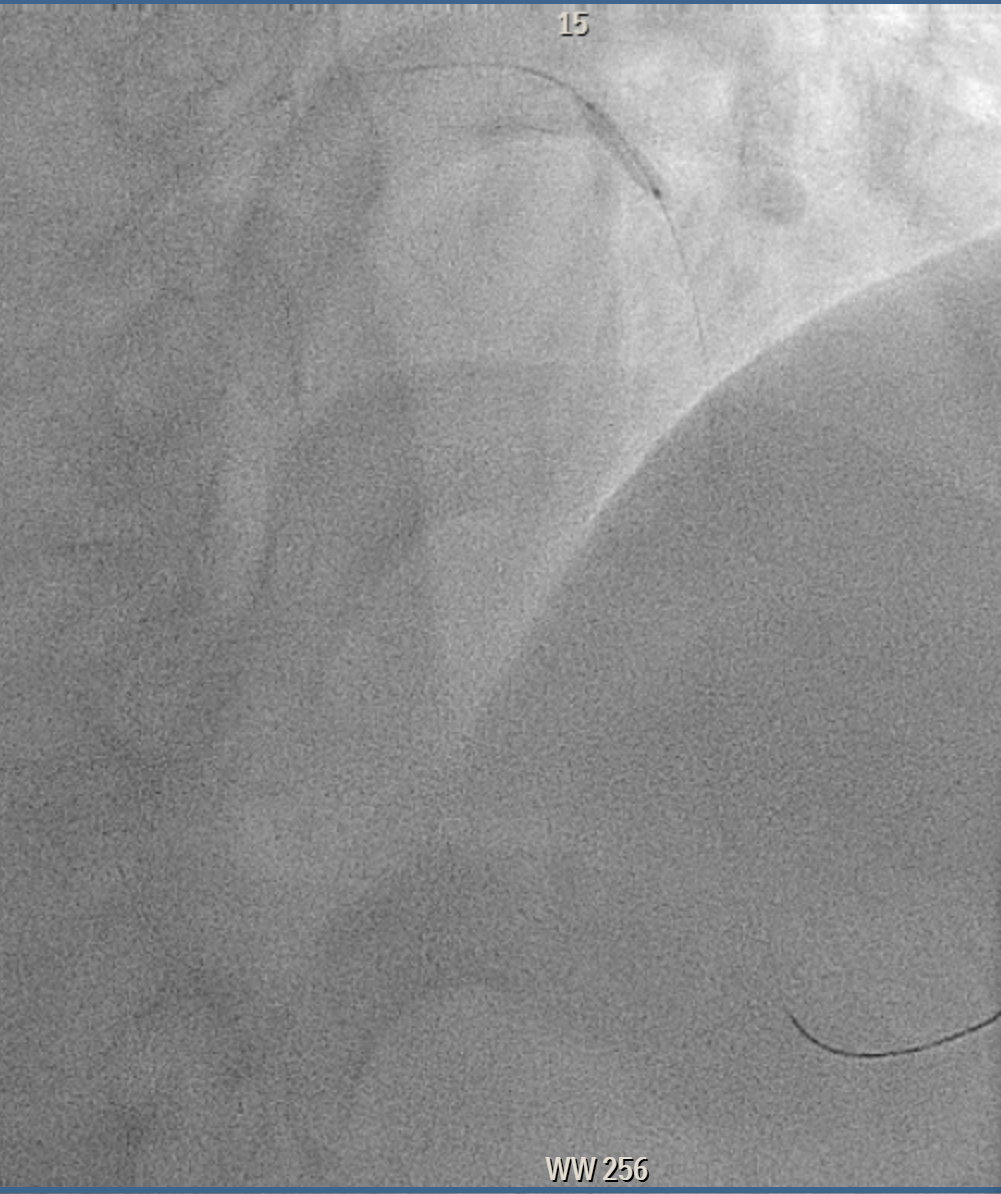

Elective angiogram was performed 3 months later as he declined procedure during index admission. Coronary angiogram showed total occlusion of proximal LAD at bifurcation of first diagonal and first septal branches. It received collateral supply from conus branch and first septal branch (Rentrop 2). J-CTO score was 2, and PROGRESS-CTO score was 1, indicate moderate complexity. Additionally, RCA was huge and dominant, while proximal first OM branch of LCX was 80–90% diseased.